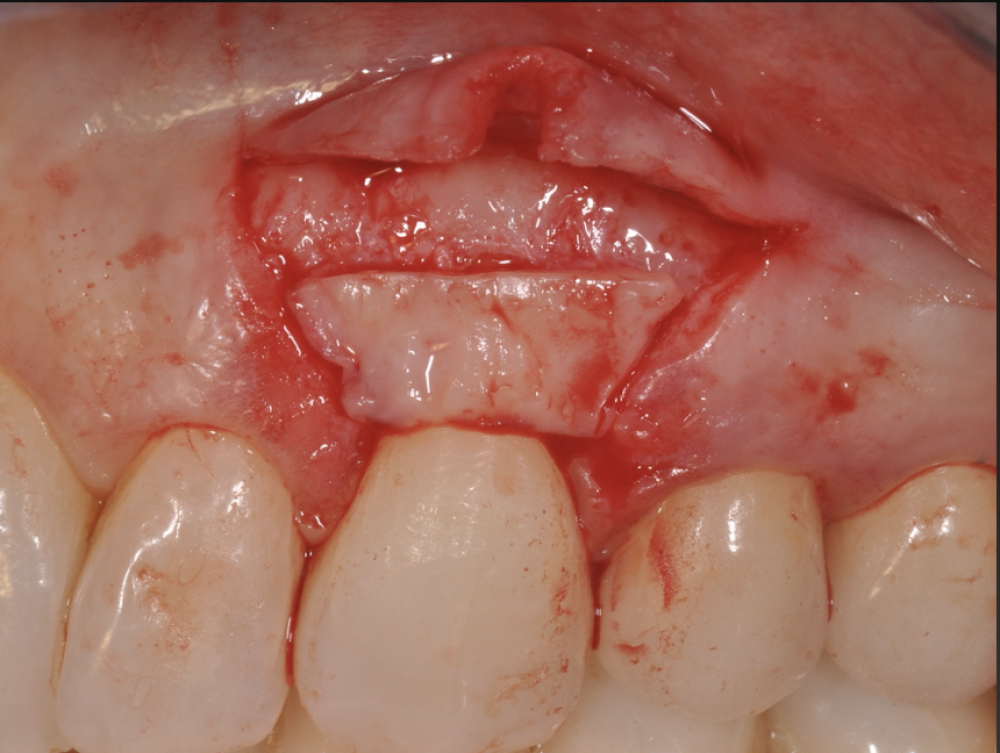

This intensive 4-day course focuses on 3 main objectives:

1. The acquisition of the state of the art knowledge and competence on advanced

periodontal surgery and microsurgery.

2. The practical application on patients in 3D live surgery.

3. The acquisition of the skills to apply them on the solution of clinical cases.